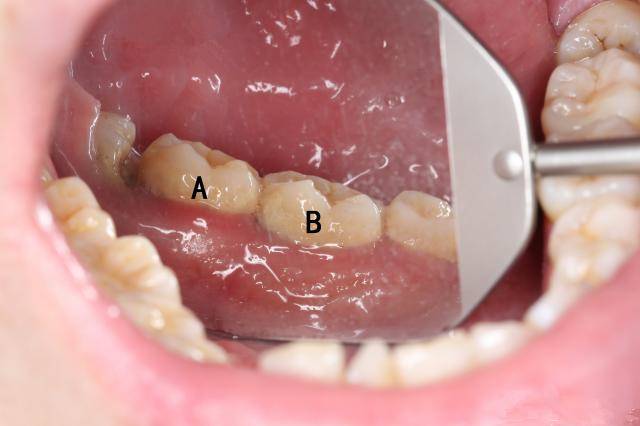

下图标注的A、B两颗牙齿表面看上去都没什么特别严重的问题。

如果我说下图中的牙齿是A、B牙齿中的一颗,你来猜猜是哪颗?

你需好奇,到底是那颗牙居然这么严重。但是牙齿表面看上去一点问题都没有,对不对?这颗牙其实是上边图中的B牙。

估计很多人都觉得不可思议,这两颗牙看着都没那么脏啊?看着不脏,龈下却已经积满牙结石。而龈下结石可比龈上结石可怕的多,轻则牙龈出血,重则造成牙槽骨吸收,导致牙齿松动脱落等。要知道牙槽骨一旦发生吸收,那就很难再生了,而如果牙槽骨发生了吸收,你觉得牙齿还能稳固吗?